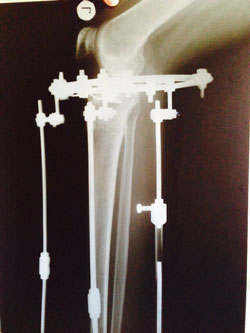

Рентген в 90 дней.

Здравствуйте,Rozali! Приезжайте на снятие аппаратов. Всё отлично! Пересрослось!!!Здравствуйте. Высылаю снимки. Как сращение? Могу приезжать на снятие?